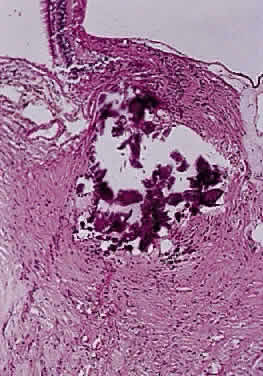

Drusen are calcific bodies that may be pre- or postlamina (Fig. 10). Those that are anterior to the lamina are usually bilateral and thought to result from mitochondrial calcification within the axons, which accompanies disturbance in axoplasmic flow. The presence of drusen may cause enlargement of the papilla and may be mistaken for papilledema (Fig. 11). Drusen may be idiopathic or occasionally inherited in an autosomal dominant pattern. The giant drusen of tuberous sclerosis are calcified astrocytic hamartomas (Fig. 12). An association with hypertension and vascular occlusion has also been noted.

Fig. 10. Calcified drusen is present in optic disc (longitudinal section hematoxylin and eosin staining).

Fig. 12. Giant calcified drusen is present anterior to laminar cribrosa. Patient had tuberous sclerosis (longitudinal section hematoxylin and eosin staining).